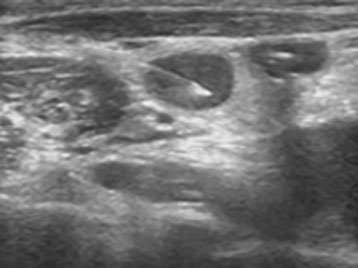

Ultrasound guided FNAC (procedure)

Procedure in which 2 or 3 small pieces of tissue are taken with help of fine needle or biopsy needle under ultrasound guidance or CT guidance and local anaesthesia.